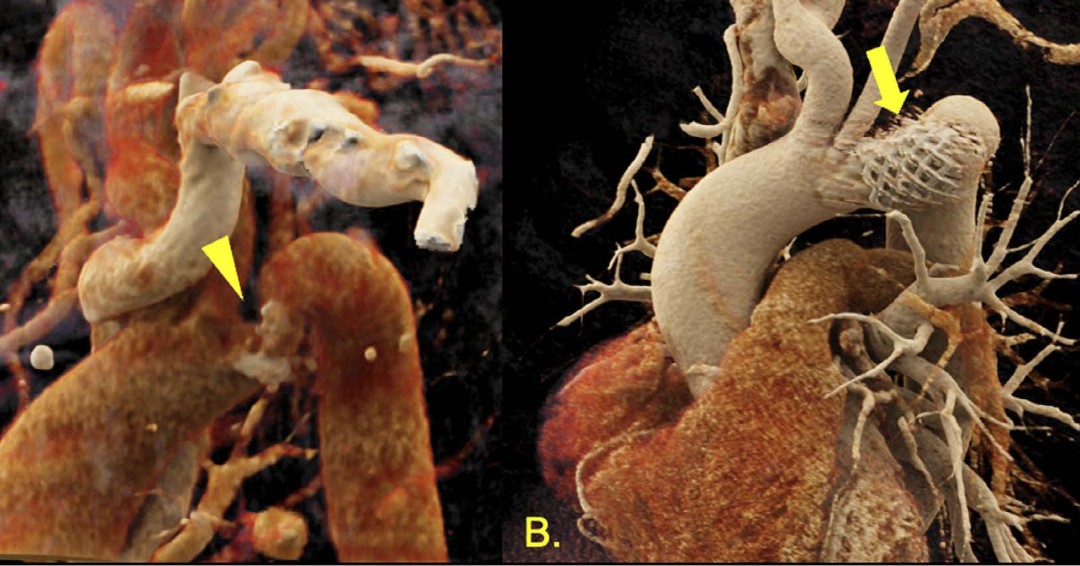

Another resident highlight! This time the spotlight is on Zhihao Zhu, a current PGY3, presenting some interesting congenital cardiac cases at PICS Society 2022 in Chicago. Nice work, Zhihao! 👏🏼 Zhihao Zhu C. Huie Lin MD, PhD DeBakey CV Education - World Class CV Training

As the population of patients with #ACHD grows, the potential need for transcatheter interventions increases. "Percutaneous Structural Interventions in Adult Congenital Heart Disease" by Rody Bou Chaaya Zhihao Zhu Valeria Duarte MD MPH C. Huie Lin MD, PhD #DeBakeyCVJournal doi.org/10.14797/mdcvj…